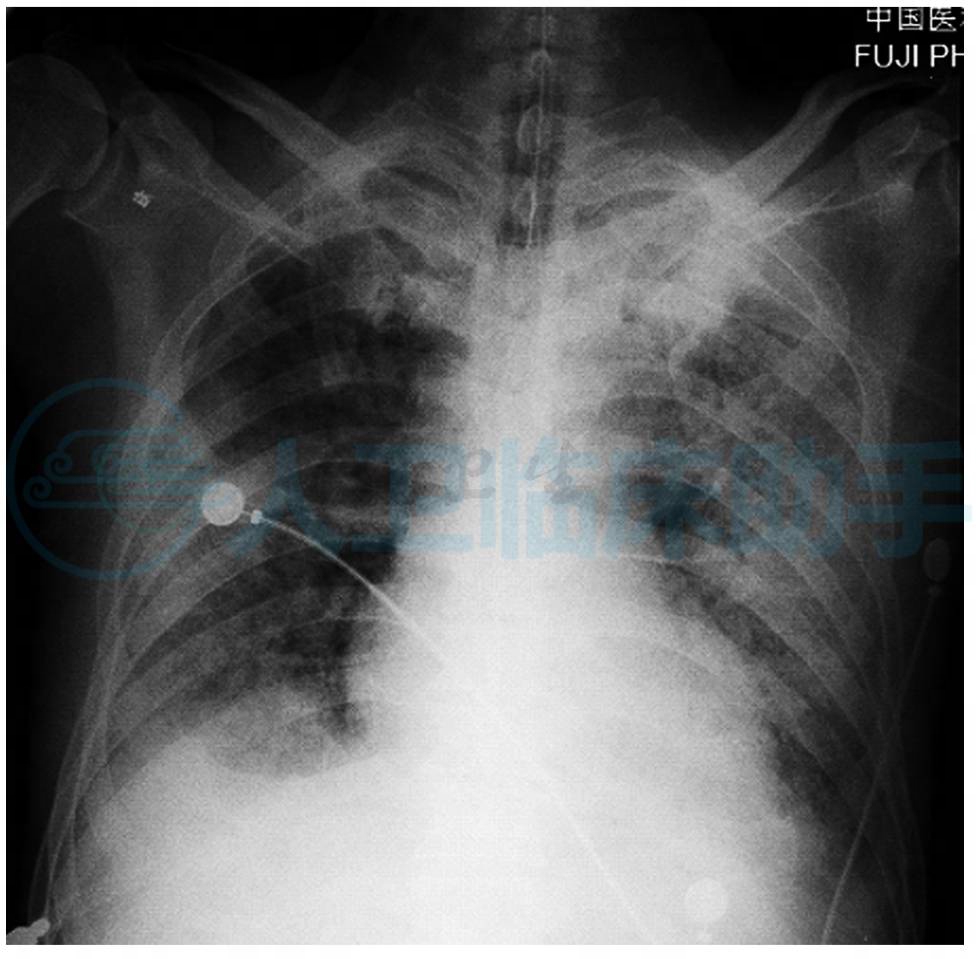

入院第9天:患者突发咯血伴有呼吸困难血氧下降,指脉氧下降至50%(图3),神志尚清,立即给予气管插管呼吸机辅助通气,并复查血常规及肾功能,化验回报:血常规:白细胞:25.8×109/L,中性粒细胞百分比90.4%,血红蛋白102g/L,血小板419×109/L,肾功能:肌酐779μmol/L,尿素氮29.3mmol/L。调整治疗方案为:甲泼尼松龙500mg日一次静点连3天,环磷酰胺0.6g日一次静点连2天,亚胺培南/西司他丁1.0g q8h静点,丙种球蛋白20g日一次静点连5天,并给予血浆置换2000ml日一次治疗共5次,连续性血液净化治疗日一次及营养支持治疗。

图3 双肺野透过度明显降低,多发渗出及斑片影